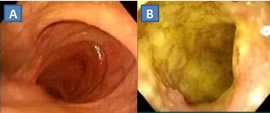

Η ελκώδης κολίτιδα είναι χρόνια, υποτροπιάζουσα, ιδιοπαθής, διάχυτη φλεγμονώδης και ελκωτική νόσος του κόλου και του ορθού. Ιστολογικά, εντοπίζεται στο βλεννογόνο και στην υποβλεννογόνια στιβάδα. Μακροσκοπικά, προσβάλλει, κατά συνέχεια ιστού, άλλοτε άλλο μήκος του παχέος εντέρου (συχνότερα ορθοσιγμοειδίτιδα, με προσβολή ορθού σε 95% των περιπτώσεων) και ολόκληρο το παχύ έντερο…